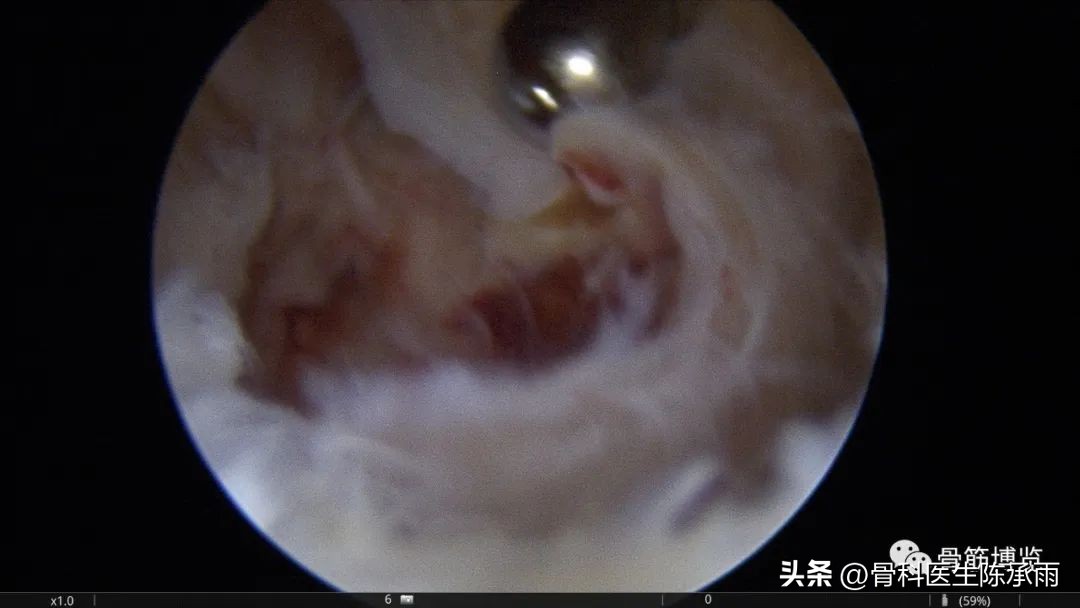

本例为内侧半月板前角巨大囊肿,关节镜下行半月板囊肿引流减压+囊肿前壁及囊壁滑膜切除+半月板缝合术。术中切除全部囊壁内滑膜及前壁及大部分后壁,保留部分后壁组织,以保证半月板前角缝合可靠及稳定。

术中情况

半月板囊肿分型决定了治疗方法的选择,对于前两种半月板囊肿因伴有半月板的损伤治疗方法相对复杂,半月板囊肿合并的半月板损伤多为水平撕裂或复杂撕裂,而且病史较长,因此需严格掌握缝合手术的指证。手术操作要点:采用常规的髌下内侧和髌下外侧入路,探查关节内囊肿和半月板撕裂的大致范围;使用刨刀细致地将囊肿切除,尽量彻底切除囊壁,充分敞开囊腔,避免囊肿复发,囊肿内可有分房或分隔现象,注意避免遗漏。注意在手术时尽量保留冠状韧带,避免冠状韧带的广泛缺损;进一步仔细探查损伤的半月板组织,明确撕裂的范围在红﹣红区或红﹣白区,对于超出上述范围的损伤或半月板的复杂撕裂及水平撕裂,放弃缝合手术,如条件许可时可在切除部分半月板(如切除水平撕裂的两片中不稳定的一片)的基础上进行缝合手术。然后以刨刀或磨钻小心修整损伤的半月板组织,使对合面整齐并显露新鲜组织;髌下外侧人路置人工作套管,附加经髌韧带的正中入路,严格解剖复位。经正中人路置人探针,固定半月板撕裂部位,使用肩袖缝合器经髌下外侧入路工作套管,缝合器尖端首先由半月板前缘和冠状韧带的交界处穿人半月板下表面后,越过半月板裂隙,在对侧由下到上穿出半月板上表面,经工作套管将线导出,体外打 Duncan 结,推线器将线结推人至半月板前缘处拉紧,再打两个套结,剪断缝线。两缝线之间间距8 mm 。滑膜囊肿的手术操作相对简单:镜下切除囊肿后,将半月板与冠状韧带之间的缺损区缝合。